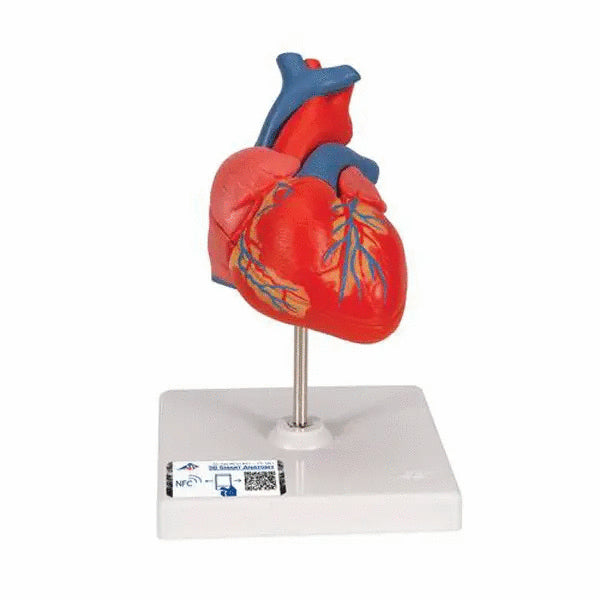

- inima (2 parti);

Fiecare model anatomic original 3B Scientific® va ofera acces direct la geamanul sau digital pe smartphone, tableta sau desktop.

Pentru a incepe, scanati codul QR situat pe modelul anatomic 3B Scientific®, descarcati aplicatia 3B Smart Anatomy si pasiti in lumea virtuala a anatomiei umane.